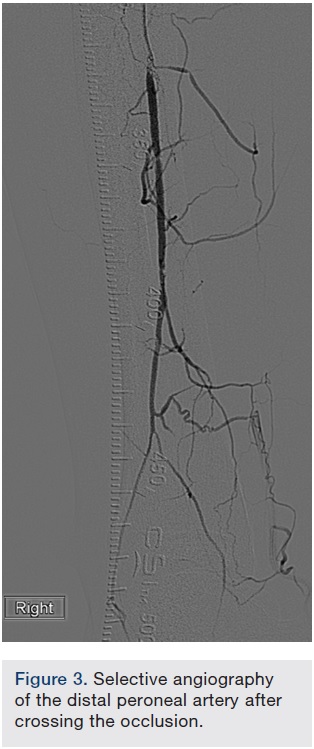

CTO crossing. The use of ultrasound (US) in gaining access to any vascular bed has been shown to be safe and effective. In addition, it is our experience that extra vascular US (EVUS) can also guide CTO crossing and therapy delivery. In this case, a .035-inch Navicross catheter (Terumo) was used to advance through the CTO in a rotational fashion. EVUS allowed us to guide the catheter and navigate the CTO (Figure 2). We were successful in crossing the CTO in the popliteal and peroneal arteries. Once crossing to the distal peroneal was confirmed (Figure 3), we started preparing for therapy.